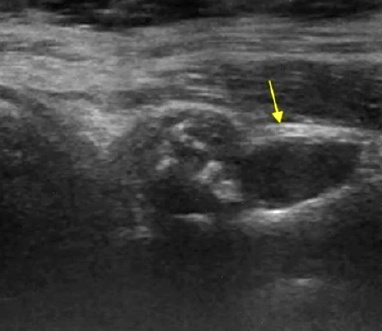

ECOGRAFÍA DE UN LABRUM CON QUISTES

Con esta imagen puede que no te quede muy claro qué es lo que estás viendo. ¡Te ayudamos un poco!

El labrum debería estar donde te hemos dibujado el triángulo (rosa).

Este labrum se ha fragmentado y el desprendimiento de éste se encuentra repartido en la parte posterior (amarillo), envuelto además de una serie de quistes paralabrales (azul)

Por aquí otro ejemplo de lesión labral, lo que vemos es una fragmentación del labrum (flecha amarilla).

Este tipo de lesiones, no suelen comprometer a la biomecánica del hombro, a diferencia de la anterior que te hemos mostrado.

Cuando existen quistes labrales múltiples, las ramas nerviosas articulares pueden ver alterada su conducción y como consecuencia, ser potentes fuentes nociceptivas.